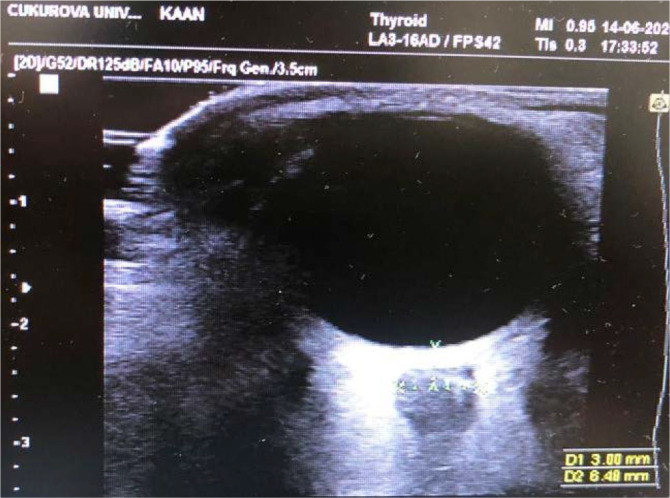

Material and method: Twenty-eight patients with head trauma who were followed up in our tertiary PICU between 2018 and 2020 were included in the study. Cerebral tissue oxygenation, optic nerve sheath diameter (ONSD), Glasgow coma score (GCS) and Glasgow Outcome Score (GOSE) values were obtained from retrospective file records and examined.

Results: Male gender was 71.4% (n=20). When we classified TBI according to GCS, 50% (n=14) had moderate TBI and 50% had severe TBI. On the first day in the poor prognosis group, ONSD and nICP were found to be higher than in the good prognosis group (for ONSD, p=0.01; and for nICP, p=0.004). On the second day of hospitalization, the ONSD and nICP were significantly higher in the poor prognosis group than in the good prognosis group (for ONSD p=0.002; and for nICP p= 0.001). Cerebral tissue oxygenation values measured on the first and second days decreased significantly on the second day in both the good and poor prognosis groups (p=0.03, 0.006). In the good prognosis group, a statistically significant decrease was found in ONSD and nICP measurements taken on the 2nd day compared to the measurements taken at the time of hospitalization (for ONSD p=0.004; for nICP p<0.001).